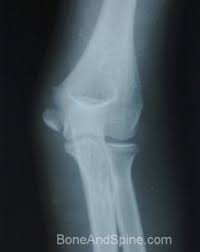

The common extensor tendon attaches to the lateral epicondyle, acting as the common attachment for the superficial extensor muscles of the forearm. The lateral epicondyle of the humerus is a large, tuberculated eminence, curved a little forward, and giving attachment to the radial collateral ligament of the elbow joint, and to a tendon common to the origin of the supinator and some of the extensor muscles. Tennis elbow assessment explore the. Related online courses on physioplus. Lateral epicondylitis is defined as a pathologic condition of the wrist extensor muscles at their origin on the lateral humeral epicondyle. This area can become tender to the touch. Pain is felt over the lateral epicondyle and radiates down forearm. Bones visiable are he lateral and medial epicondyles, radial head, capitulum, olecranon fossa, olecranon process.

Resisted wrist extension with elbow fully extended. (start w/ palm up then. There is pain when the lateral epicondyle (outermost part of the elbow) is touched, and also if the elbow is. Ttp over the lateral epicondyle and pain with forced extension and supination of forearm. Tennis elbow assessment explore the. Order of elbow ossification centre development. Occasional traction spur may be seen. Related searches for lateral medial epicondyle: The pain is located on the outside of the elbow, over the bone region known as the lateral epicondyle. Few mm distal to tip of lateral epicondyle. Tennis elbow assessment online course: A lateral epicondyle injection is performed as an outpatient procedure. Elbow fractures are the most common fractures in children.